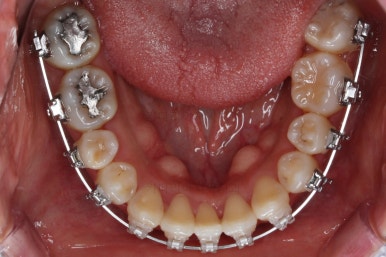

사용한 장치 : 자가결찰 세라믹(클리피씨) + 미니스크류

아랫니는 최대한 추가 발치 없이 후방의 송곳니를 당겨와서 앞니 역할을 하게 했습니다.(총 4개 앞니처럼)

부분적으로 장치 셋팅을 다시 해줬고요.

밀고 당기기를 위해서 미니스크류를 셋팅했고요.